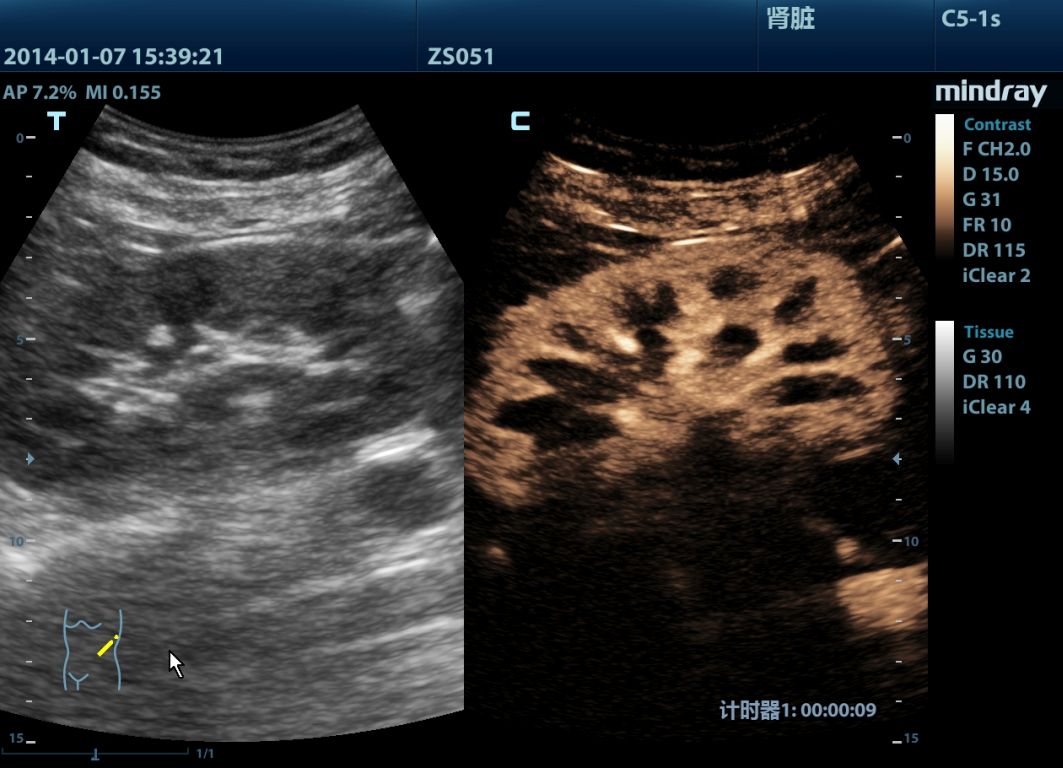

Mindray M9 je dopplerovský ultra ľahký prenosný UZV prístroj najvyššej High End triedy s použitím single crystal 3T sond (vynikajúce zobrazenie blízkeho i vzdialeného poľa), HDR FLOW, ECHO BOOST, Natural Touch Elastography, kontrastného zobrazenia, TDI. Špeciál hlavne pre kardiológiu.

Klinické obrázky: